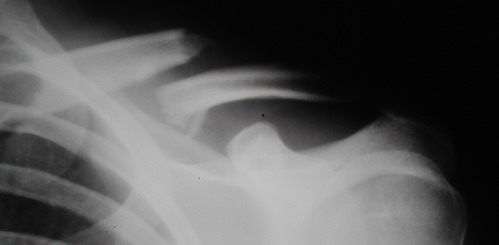

Во время стажировки в Австрии не мог не поинтересоавться, как австрийские хирурги лечат переломы ключицы. Оказалось, при переломах без смещения или с небольшим смещением накладывают восьмиобразную повязку, в остальных случаях выполняют остеосинтез пластинами.